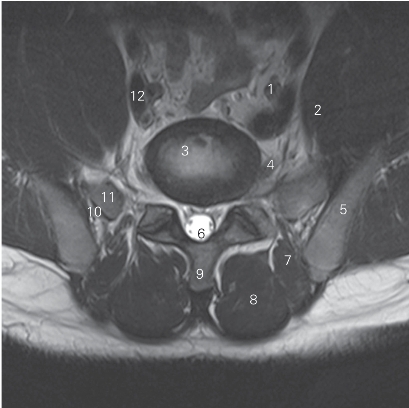

图3-10 经第5腰椎间盘的横断层MR T2加权图像

1 髂总动脉 common iliac artery 2 腰大肌 psoas major

3 第5腰椎间盘 5th lumbar intervertebral disc

4 第5腰神经 5th lumbar nerve 5 髂骨 ilium

6 硬膜囊 dural sac 7 竖脊肌 erector spinae

8 多裂肌 multifidi 9 腰椎棘突 lumbar spinous process

10 骶髂关节 sacroiliac joint 11 骶翼 ala of sacrum

12 髂总静脉 common iliac vein